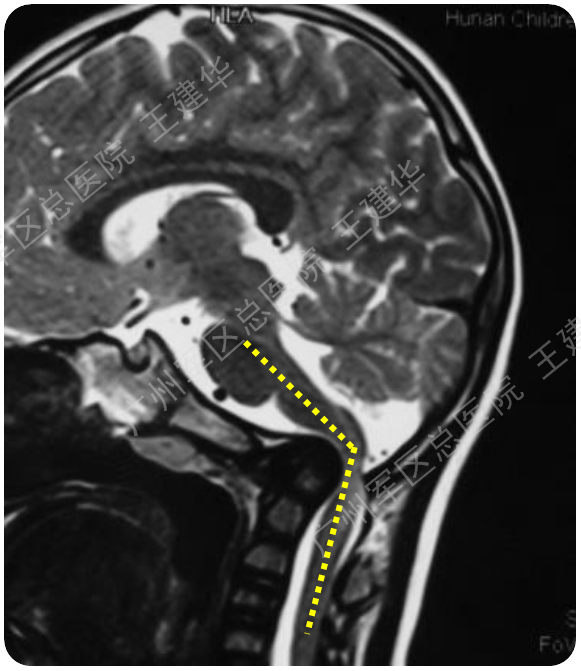

颈椎MR检查提示:颈椎上端结构陷入枕骨大孔,脑干受压变形

陷入枕骨大孔的寰椎和齿突已经下拉复位,枕颈排列恢复正常

可以看到:

脑干压迫解除,延髓脊髓角恢复正常